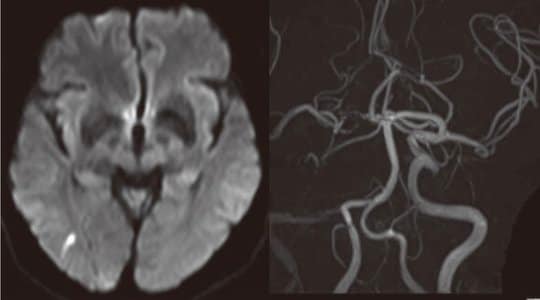

これは50代後半男性(図2)の症例です。

来院までの経過:左の手や足がしびれて、眼の症状もあった。かげろうが上がるようになり、そうして霧がかかったように見えなくなる。これが来るとしびれたようになる。眼は左から始まって、全体に霞みがかかるような感じがある。目の症状が出ると必ずしびれが出る。最終は来院5日前。以前は眼の症状はなかった。ここ最近は症状が強かったため来院。

既往歴:高血圧(177/104,96)、高コレステロール血症、高尿酸血症、閉塞性動脈硬化症。

左図:MRI拡散強調画像 右後頭葉に高信号域を呈する小さな脳梗塞(皮質枝閉塞)。

右図:MRA右内頸動脈閉塞、右中大脳動脈も写りが悪い。